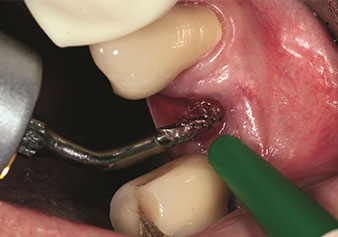

W&H also offers the perfect solution for the internal sinus lift.

Following preparation of the maxillary sinuses with the corresponding instrument set (Fig. 3), the new Z35P instrument (Fig. 4) is used to lift the membrane hydrodynamically. The same instrument set can also be used for piezosurgical preparation of the implant bed in increasing diameters (Figures 3 and 4 included with the kind permission of Dr Mario Kirste, Frankfurt/Oder).

Preparation of maxillary sinus floor and lifting of Schneiderian membrane (Z35P instrument)

Fig. 4: Preparation of maxillary sinus floor and lifting of Schneiderian membrane (Z35P instrument). Photo: © Dr Mario Kirste (Frankfurt / Oder)